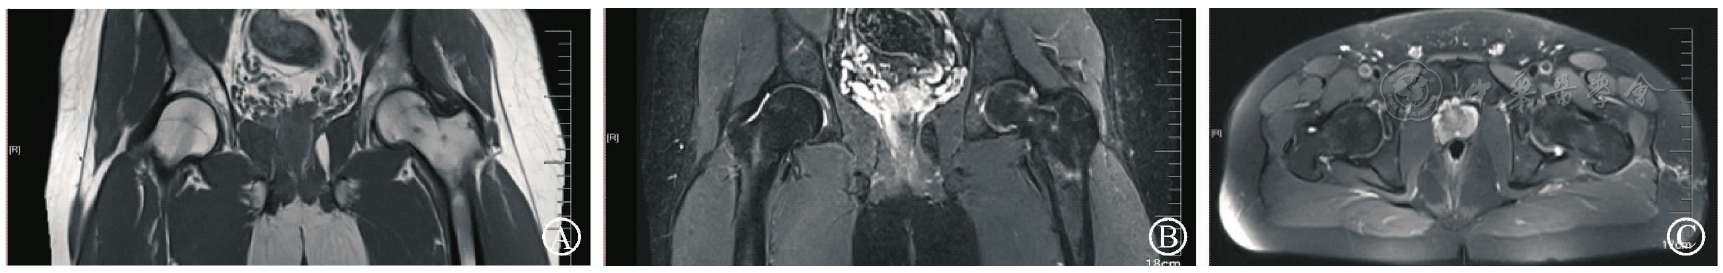

图4 2019年1月就诊时双髋MRI。图A为双髋MRI冠状面T1WI像,示右侧股骨头颈部骨髓水肿;图B为双髋MRI冠状面STIR像,示右侧股骨头颈部骨髓水肿;图C为双髋MRI横截面STIR像,示右侧股骨头颈部骨髓水肿

图5 2019年6月复查双髋MRI。图A为双髋MRIT1WI像冠状面无骨髓水肿;图B为双髋MRI冠状面STIR像无骨髓水肿;图C为双髋MRI横截面STIR像无骨髓水肿